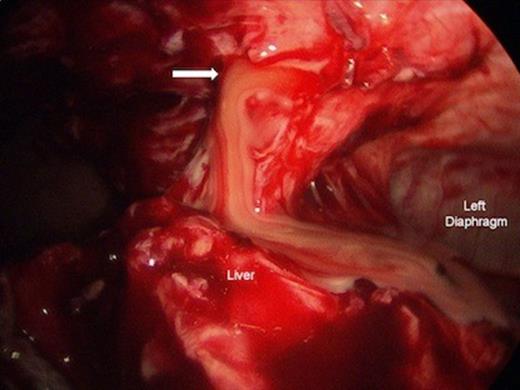

Axial CT Chest showing anterior inferior mediastinal abscess (Arrow).

Laparoscopic drainage of anterior inferior mediastinal abscess. Left diaphragm and liver are shown. Arrow = Mediastinotomy.